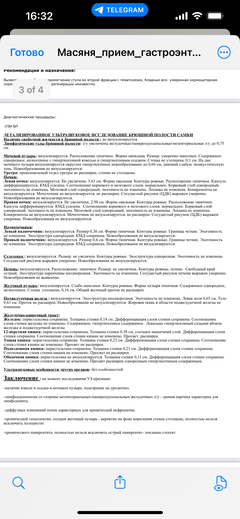

Была куплена в питомнике взрослой. У Масяни начались проблемы с кишечником и она стала подтекать и все пачкать. Надо отдать должное хозяевам - ее обследовали вдоль и поперек - как говорили местные врачи, сдавали много анализов но диагноза так и не поставили.

Ярко выраженная болезненность в области крестца, на обезболе полегче. По результатам приема невролога проведена миелография - множественная компрессия, возможно опухоль, возможно грыжа, нужно удалять...